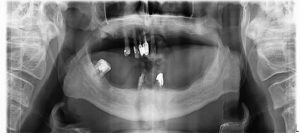

Radio panoramique de la situation de départ :